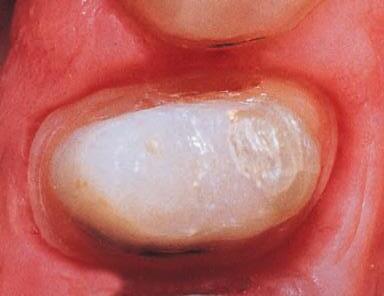

Remove or significantly reduce mild to moderate decalcification with a few applications of

1. realityesthetics.com. 2. Celik EU, et al. Clinical performance of a combined approach for the esthetic management of fluorosed teeth: three-year results. Niger J Clin Pract. 2017:20(8);943–951. 3. Da Silva Machado J, Cândido MS, Sundfeld RH, De Alexandre RS, Cardoso JD, Sundefeld ML. The influence of time interval between bleaching and enamel bonding. J Esthet Restor Dent. 2007;19(2):111–119. doi:10.1111/j.1708-8240.2007.00077.x. 4. Spyrides GM, Perdigão J, Pagani C, Araújo MA, Spyrides SM. Effect of whitening agents on dentin bonding. J Esthet Dent. 2000;12(5):264–270. doi:10.1111/j.1708-8240.2000.tb00233. 5. Unlu N, Cobankara FK, Ozer F. Effect of elapsed time following bleaching on the shear bond strength of composite resin to enamel. J Biomed Mater Res B Appl Biomater. 2008 Feb;84(2):363–368. 1

2. After rubber dam placement, apply Opalustre slurry to discolored enamel using the syringe.

3. Use OpalCups™ Bristle cup to compress Opalustre slurry on tooth surface using medium to heavy pressure. Suction the paste from the teeth then rinse, evaluate, and repeat as necessary. Finish treatment by polishing with OpalCups™ Finishing cup.

4. After enamel microabrasion and 21 days of using Opalescence™ whitening gel.